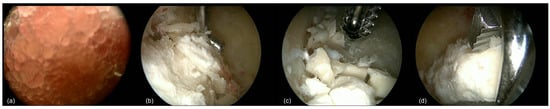

Figure 2.

After the introduction of the scope into the bone cavity, vision was often impaired by fat tissue in the case of IOL (a). After thorough irrigation and endoscopic removal of the fat tissue using an arthroscopic shaver, residual calcifications were removed using an arthroscopic grasper or shaver (b–d).